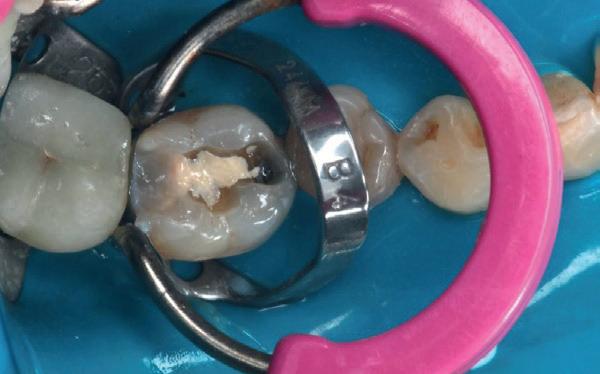

Deze 51-jarige vrouw werd verwezen omwille van pijnklachten met de vraag of een wortelkanaalbehandeling nog mogelijk was, of dat er eerder naar extractie gekeken moest worden (foto 7). De tand testte nog vitaal tijdens de consultatie dus ik besloot om eerst de vulling te verwijderen. Het bleek een typische “cracked tooth” (foto 8-9). Ik besloot om de tand te voorzien van een adhesieve stompopbouw (foto 10). En bij de opvolging zes maanden later (foto 11) was de patiënt al die tijd klachtenvrij en kreeg de tandarts groen licht om verder te gaan met een indirecte restauratie. Geen wortelkanaalbehandeling en al zeker geen extractie nodig.

Elke tandarts kent het. Je hebt een endostart uitgevoerd, maar een week later komt de patiënt weer terug met klachten. Het ging de goede kant op, maar na een paar dagen kwam de pijn toch weer opzetten. ‘’Raar, ik weet toch zeker dat ik alle kanalen netjes heb gereinigd’’, denk je dan bij jezelf. Het is een soort gemeengoed geworden, om de patiënt dan tussendoor te laten komen zodat de kanalen weer gedesinfecteerd kunnen worden met natriumhypochloriet. Maar is dat wel doeltreffend? Waarom zijn die bacteriën zo snel weer van betekenis geworden? Graag leg ik kort uit hoe je deze situatie kunt voorkomen aan de hand van een eenvoudige casus uit de praktijk.

Een 58-jarige patiënt was naar onze praktijk verwezen door zijn eigen tandarts. Hij had pijn en een flinke zwelling aan element 35. Zijn tandarts had een nette endodontische opening gemaakt en het element ontdaan van al het geïnfecteerde en/of necrotische pulpaweefsel en het kanaal uitvoerig gedesinfecteerd.

Aanvankelijk ging het goed, maar na een paar dagen kwam de patiënt toch weer terug met een flinke zwelling. Ondanks herhaalde behandelingen kwam de klacht net zo hard weer terug. Dit proces heeft zich wel zes keer herhaald, zonder resultaat.

Wat direct opviel aan de meegestuurde röntgenfoto was de matige coronale restauratie. De lekkende vulling zou het pijnlijke proces dat meneer heeft doorgemaakt verklaren. Bij het spoelen van het wortelkanaalstelsel wordt dan weliswaar veel gedesinfecteerd, maar binnen de kortste keren stromen de bacteriën en het substraat via de lekkage onder de vulling doodleuk weer naar binnen!

Naast de matige restauratie kon ik verder geen open apex, verticale fractuur of een andere oorzaak ontdekken, waardoor de bacteriën in het element zich in rap tempo konden vermenigvuldigen.

Om te voorkomen dat er niet wéér een infectie plaatsvindt, heb ik tijdens het eerste consult niet alleen het wortelkanaalstelsel gedesinfecteerd, maar ook direct de coronale restauratie vervangen.

Samenvattend

Wees altijd kritisch op de coronale restauratie! Heeft de patiënt geen klachten meer gehad sinds het uitvoeren van de endostart? Dan is dit een teken dat de coronale restauratie voldoet.

Zijn de klachten wel teruggekomen of niet volledig verdwenen? Probeer dan te achterhalen waarom dit zo is. De kans is groot dat de kroon of vulling lekt of los zit.

Het vervaardigen van een niet lekkende coronale restauratie voorkomt trouwens niet alleen dat de pijnklacht op korte termijn terugkomt, maar zorgt er ook voor dat de prognose van de wortelkanaalbehandeling aanzienlijk verbetert.

Ik verwijs daarom vaak naar de systematic review en meta-analyse van Gillen et al. (2011), waarin duidelijk naar voren is gekomen dat een adequate coronale restauratie minstens zo belangrijk is als een correct uitgevoerde wortelkanaalbehandeling.